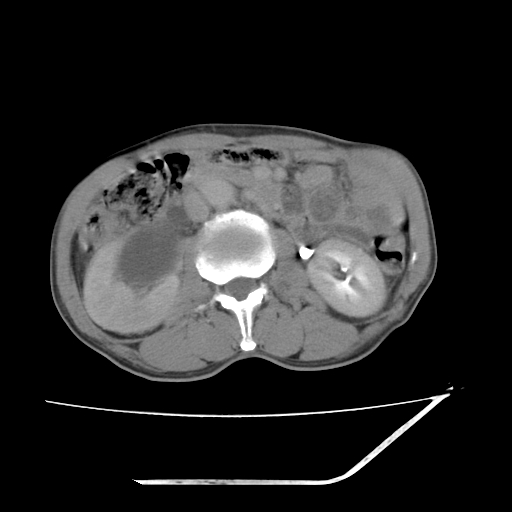

平扫

考虑右肾盂癌,肾动脉受侵,右肾功能减退,右肾盂输尿管积水,管壁增厚,考虑种植转移,应该把下面扫完的

支持右侧肾盂癌伴肾静脉瘤栓形成可能性大,右肾结石.肝右叶后段低密度影,不除外转移.

右肾盂旁ca并肾静脉瘤栓形成/肾功能降低。

右肾结石。

右肾盂癌,肾动脉受侵,右肾盂输尿管积水,管壁增厚,考虑种植转移

右肾盂移行细胞癌并右输尿管中段转移.肾积水.

支持 右侧肾盂癌伴肾静脉瘤栓形成可能性大,右肾结石;肝右叶后段低密度影,不除外转移。

1.右侧肾盂癌伴肾盂积水。

2.肾脏功能减退,原因有:(1)肾动脉受侵。(2)肾静脉受侵(3)肾积水,等。本例,肾动脉显影较好,但受压明显;肾静脉无明显显示,受压或静脉癌栓,下腔静脉腔内未见明显充盈缺损。

3.右侧上段输尿管扩张,原因:(1)积水所致;(2)种植。